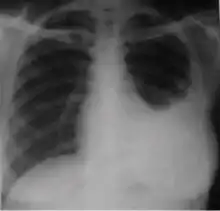

Dense homogenous opacity in right, middle and lower lobe of primary pulmonary TB.

Chest x-ray showing patchy opacification on the upper right and mid-zone lung with fibrotic shadows, as well as bilateral hilar lymphadenopathy.